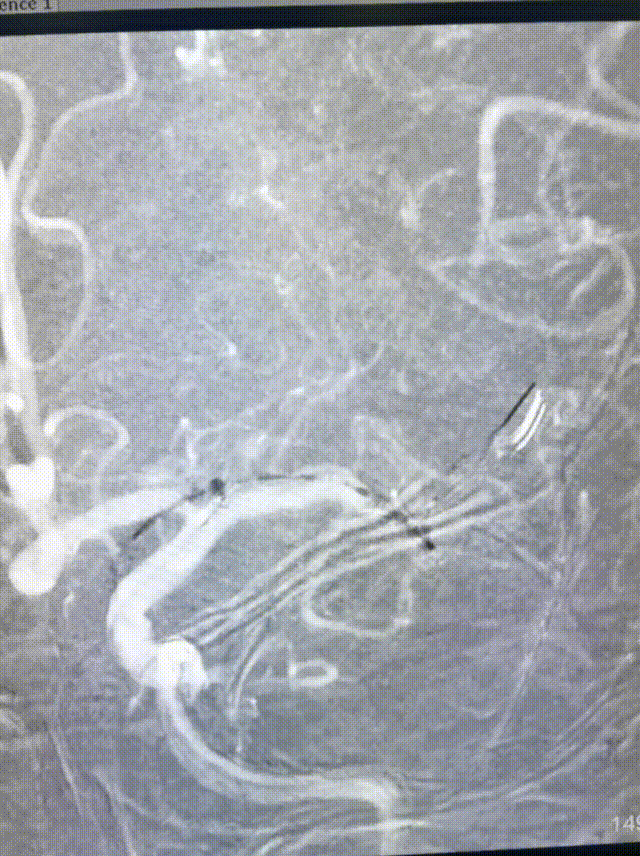

完成扩张后。

球囊泄压后利用Syphonet®取栓支架的锚定效果让中间导管靠近闭塞段;撤出快交球囊后采用SWIM技术取栓;术后造影证实血管再通。

开通后血流再次闭塞,考虑球扩后夹层形成可能;补救性予以电解脱释放Solitarie支架后正侧位造影。

支架的保护作用,头端抓捕网篮加强血栓捕获,防止碎栓逃逸。